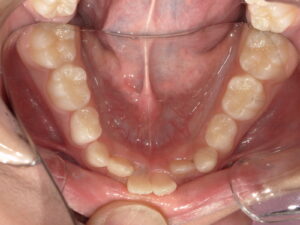

After

| 治療期間・回数 | 8ヶ月。11回。 |

| 治療方法 | リンガルアーチによる前歯の被害改善。 |

今回は骨格的には問題なく、前歯2本の歯の生える向きがずれてしまっているだけなので リンガルアーチにて上の前歯を前に押し出してあげます。

そうすることで下の前歯2本は何もしなくても自然と内側に引っ込みます。

治療前後